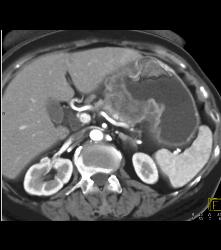

Antral Carcinoma With Adenopathy